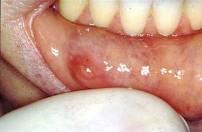

以下涎腺肿瘤最易发生种植复发的肿瘤是 ( ) A.肌上皮瘤 B.嗜酸细胞腺瘤 C.多形性腺瘤 D.腺淋巴瘤 E.基底细胞腺瘤

问题 以下涎腺肿瘤最易发生种植复发的肿瘤是 ( )

选项 A.肌上皮瘤 B.嗜酸细胞腺瘤 C.多形性腺瘤 D.腺淋巴瘤 E.基底细胞腺瘤

答案 C